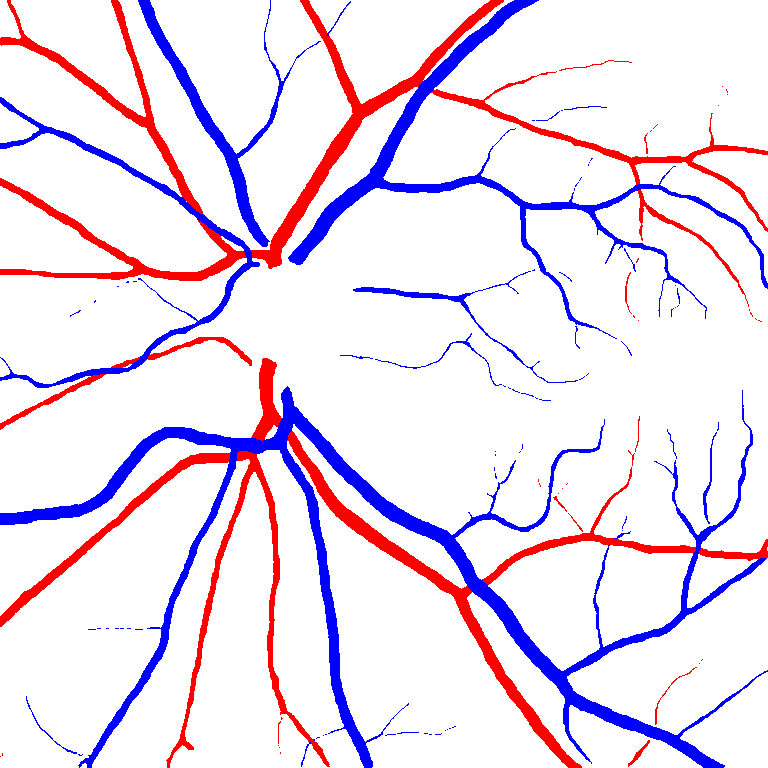

Table V presents quantitative performance benchmarks of SegRAVIR and other competing approaches for retinal artery and vein classification on the RITE dataset [11]. SegRAVIR outperforms previous state-of-the-art approaches in terms of accuracy, sensitivity, and specificity. Fig. 5 provides a qualitative comparison between segmentation outputs of SegRAVIR and the method of Hemelings et al. [40] on the RITE test set.

(a) (b) (c)

(a) (b) (c)